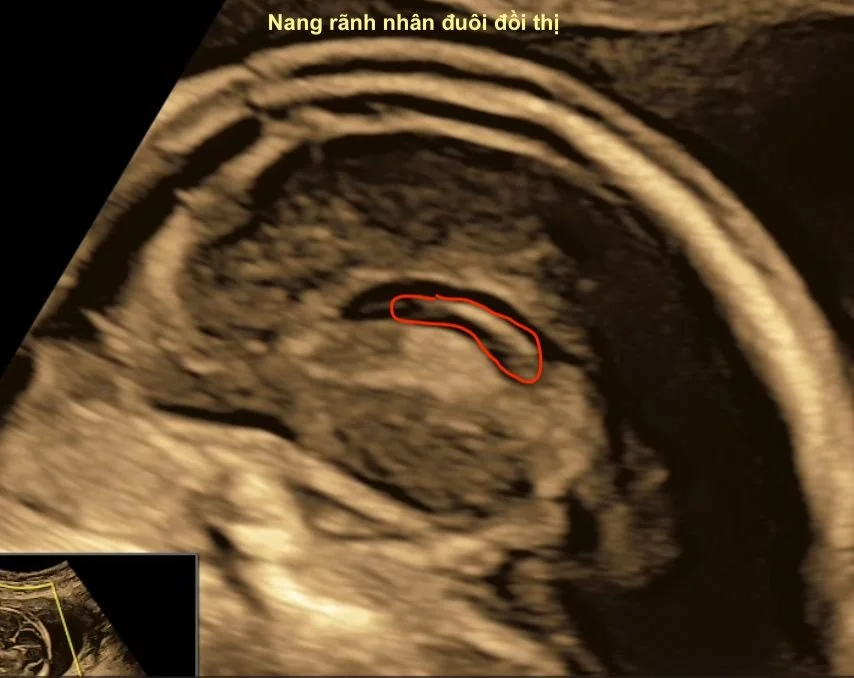

PVPC là cấu trúc dạng nang trống âm, thành mỏng, không có biểu mô lót, nằm sát não thất bên. Thường gặp ở sừng trán não thất hoặc rãnh caudothalamic. Đây là tổn thương có nguồn gốc từ sự thoái triển hoặc vi xuất huyết của vùng germinal matrix trong giai đoạn sinh thần kinh (14–28 tuần).

- Nang tròn/bầu dục, trống âm hoàn toàn, thành mỏng.

- Không thông với não thất, không gây giãn hoặc lệch đường giữa.

- Doppler: không thấy dòng chảy trong nang.

- Caudothalamic pseudocyst: tại rãnh nhân đuôi - đồi thị